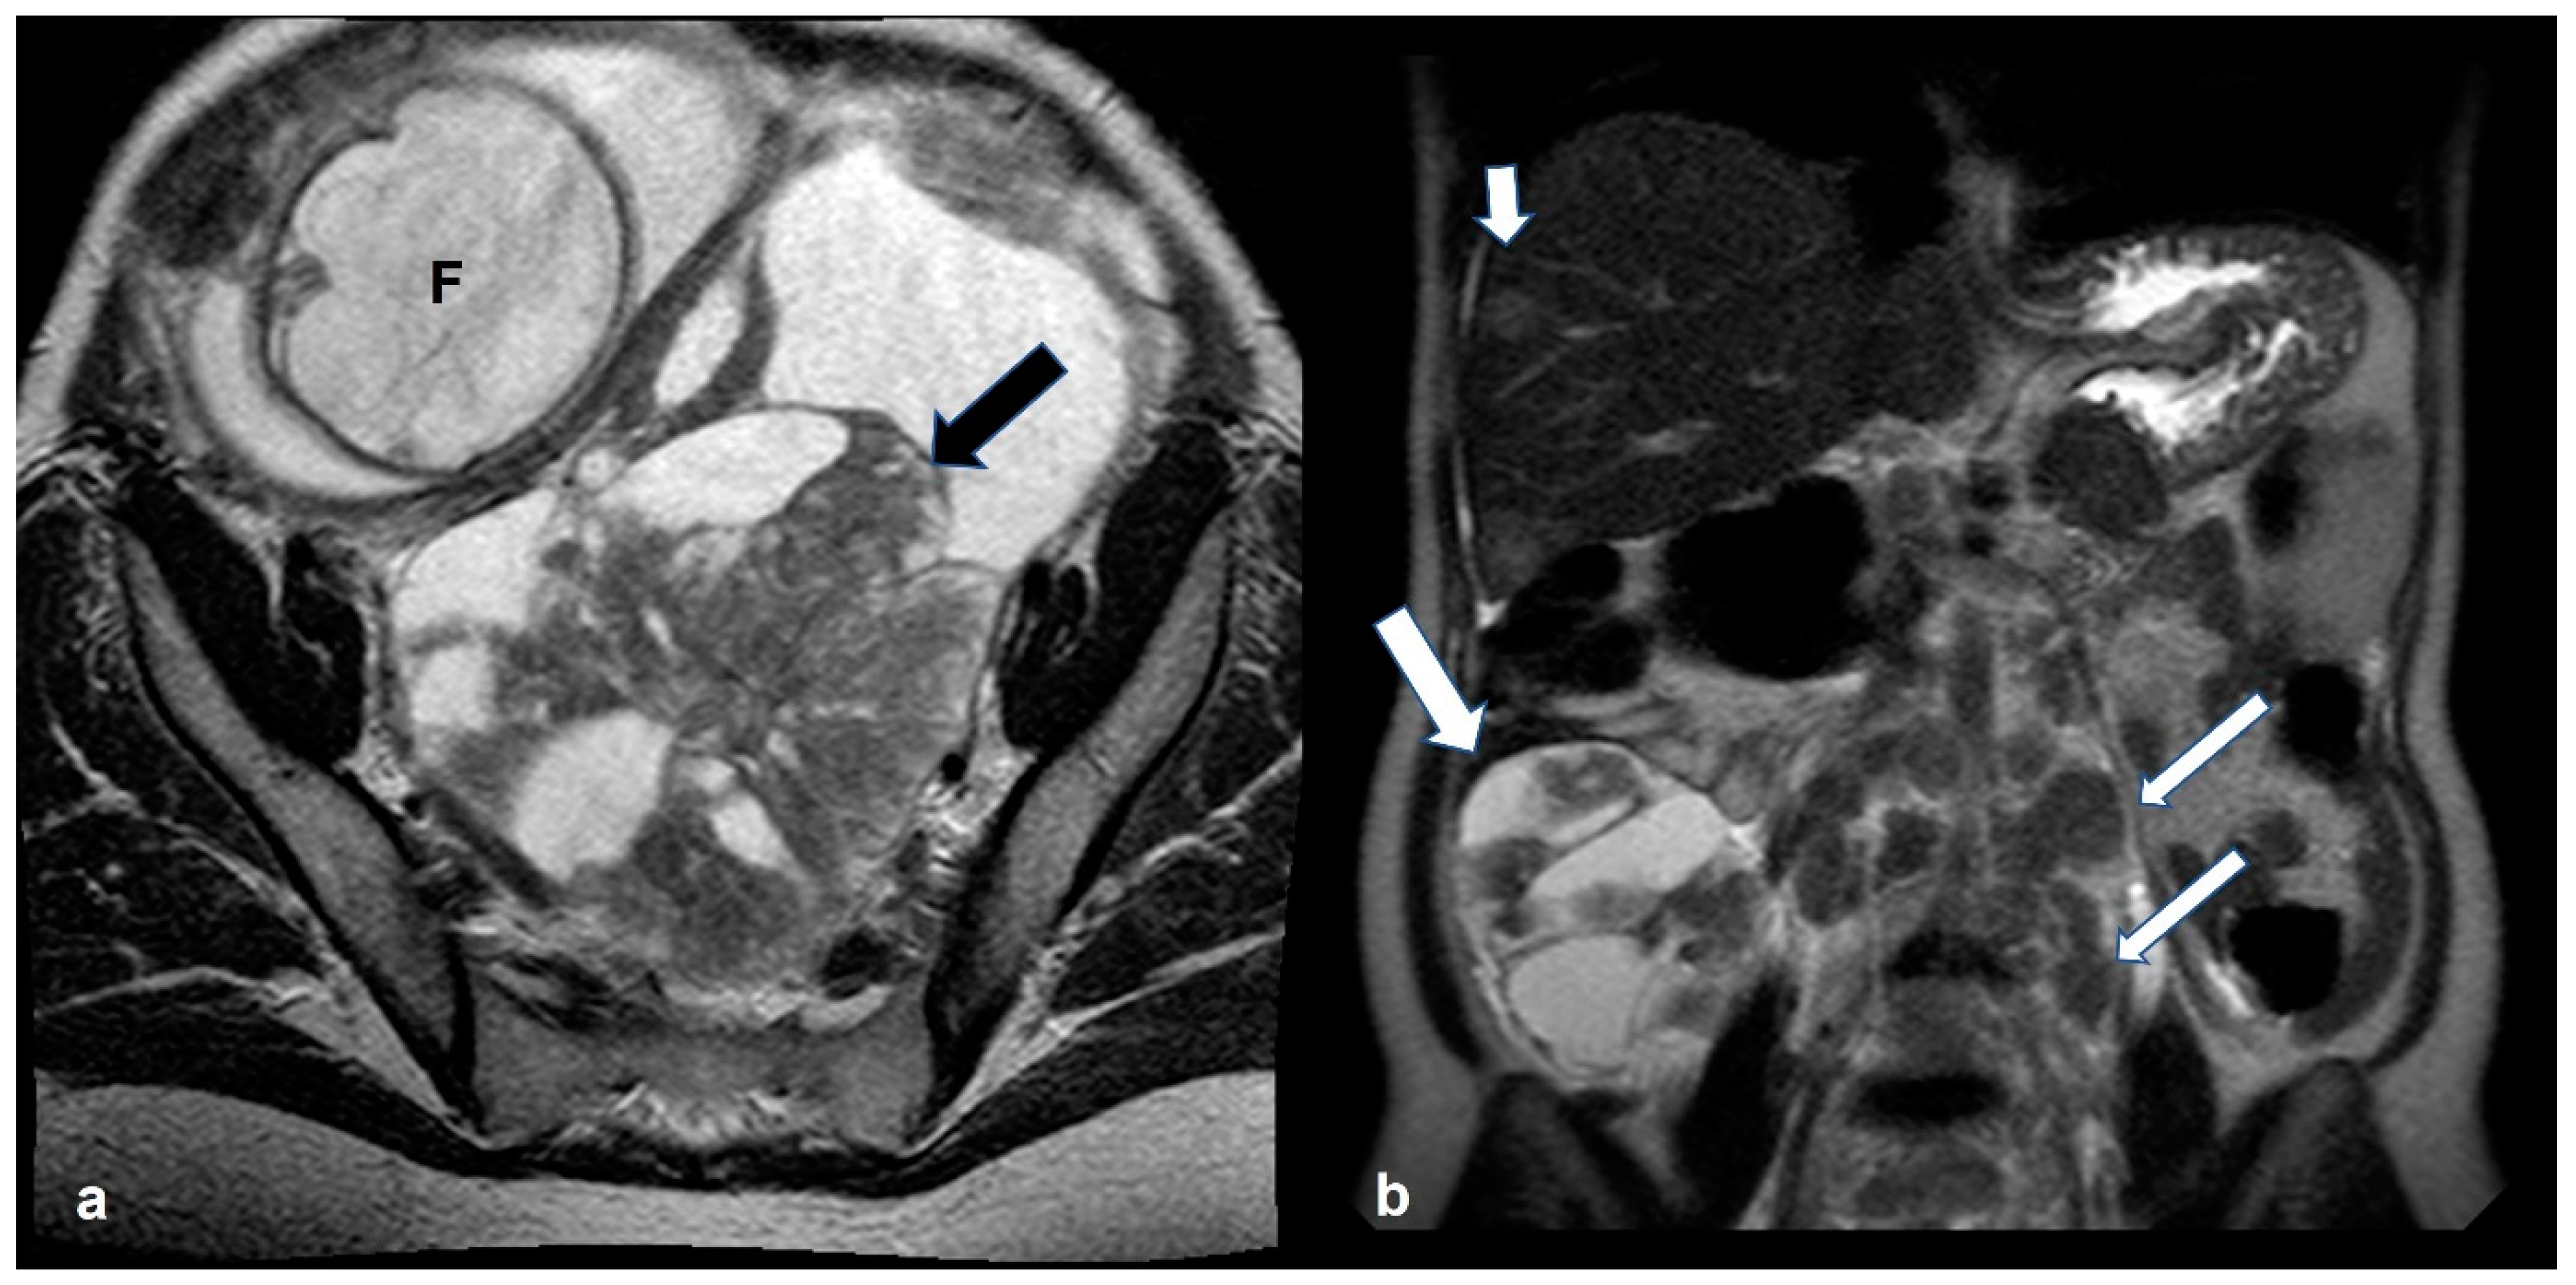

2.5. Pregnancy

2.5.3. Epithelial Ovarian Cancer